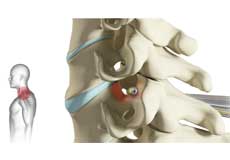

Herniated Disc (Lumbar)

Herniated disc is a condition in which the outer fibers (annulus) of the intervertebral disc are damaged causing the soft inner material of the nucleus pulposus to rupture out of its space. A herniated disc, common in the lower back (lumbar spine) occurs when there is a tear in the outer lining of the disc (annulus fibrosus). This causes the inner jelly-like material (nucleus pulposus) to leak out and place pressure on the adjacent spinal nerve root. It is the most common cause of lower back pain and pain that radiates down the leg (radiculopathy).

Lumbar Herniated Disc

A herniated disc is a condition in which the outer fibers (annulus) of the intervertebral disc are damaged, causing the soft inner material of the nucleus pulposus to rupture out of its space. It is the most common cause of lower back pain and pain that radiates down the leg (radiculopathy).

Lumbar Disc Herniation

Lumbar disc herniation is the most common cause of lower back pain and leg pain (sciatica). Aging, injury or trauma may cause the annulus fibrosus to tear, resulting in protrusion of the nucleus pulposus. This may compress the spinal nerves and/or spinal canal.

Disc Herniation

Disc herniation is a condition where the central nucleus pushes through the outer edge of the disc, causing a bulge that compresses the spinal nerves.